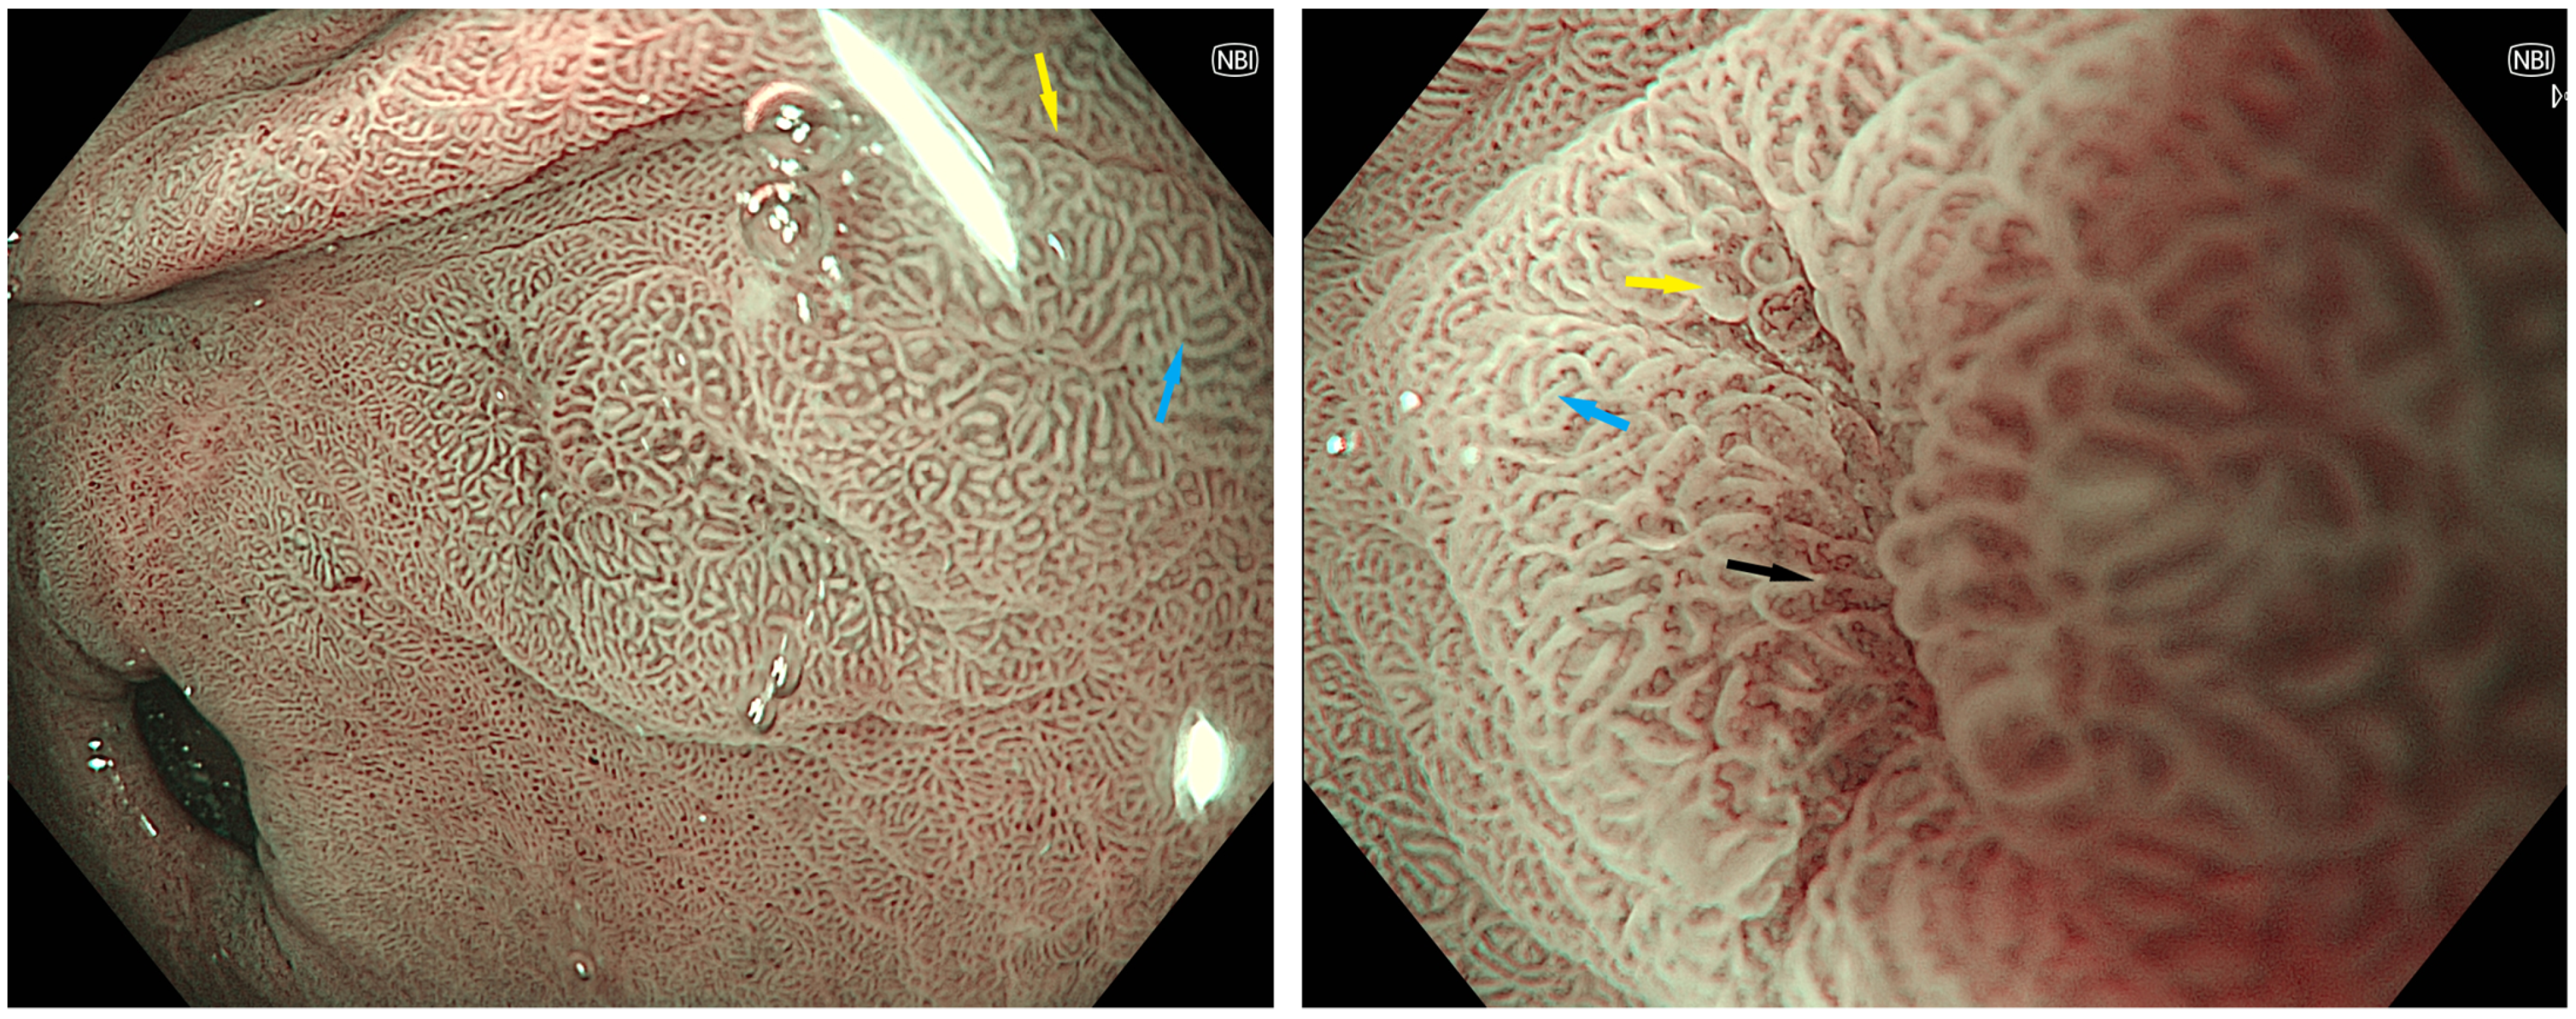

3.2. Endoscopic Features

- An, J.K.; Song, G.A.; Kim, G.H.; Park, D.Y.; Shin, N.R.; Lee, B.E.; Woo, H.Y.; Ryu, D.Y.; Kim, D.U.; Heo, J. Marginal turbid band and light blue crest, signs observed in magnifying narrow-band imaging endoscopy, are indicative of gastric intestinal metaplasia. BMC Gastroenterol. 2012, 12, 169. [Google Scholar] [CrossRef]